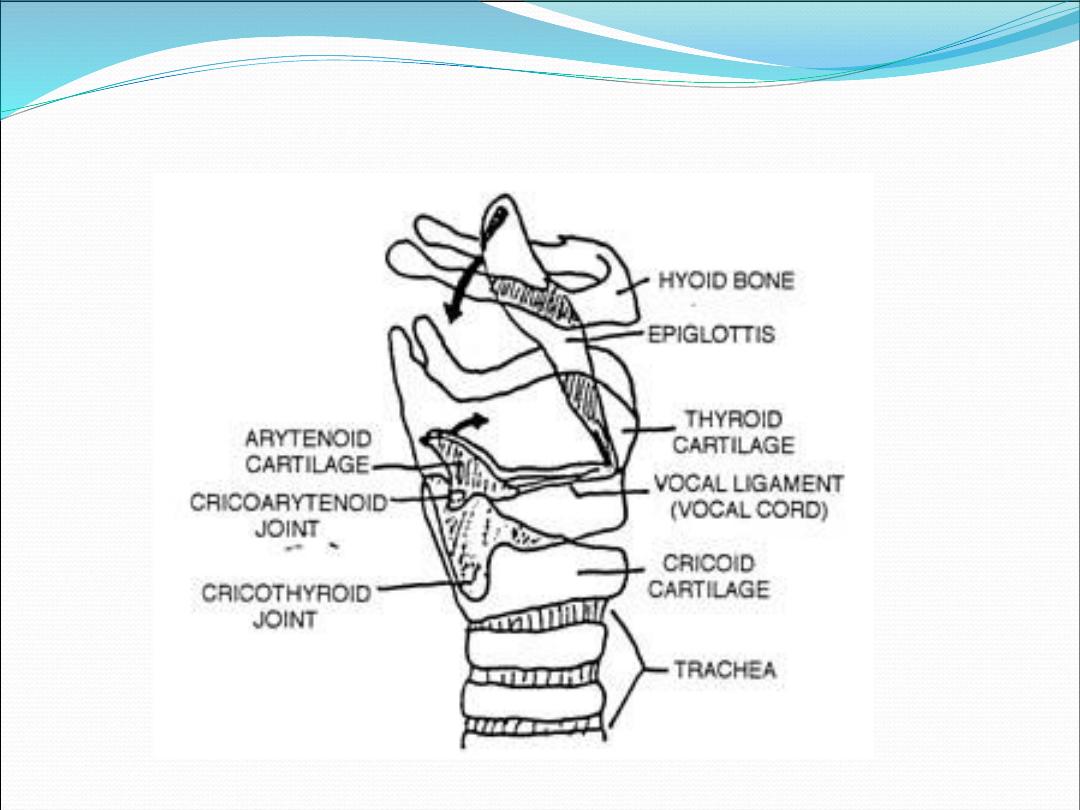

Cartilages of the larynx

1.

Thyroid cartilage (single)

2.

Cricoid cartilage (single)

3.

Epiglottis (single)

4.

Arytenoid cartilages (paired)

5.

Corniculate cartilages (paired)

6.

Cuneiform cartilage (paired

)

It is commonly described as part of the

laryngeal framework, because it is an

important point of attachment for

extrinsic muscle of the larynx

1.

Thyrohyoid membrane

2.

Cricothyroid membrane

3.

Cricotracheal ligament

4.

Vocal ligament